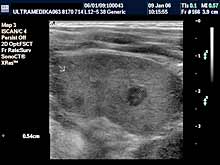

- Dojke

Pregled dojki može biti indikovan ako dolazi do naglog uvećanje

dojke ili do pojave izraštaja koji se pipa. Ultrazvučni pregled je

sigurno prva dijagnostička procedura, jer je Sono CT tehnika u

prednosti kod otkrivanja malih promena uodnosu na mamografiju, zbog

veće preciznosti, a pri tome je izbegnuto i jonizujuće zračenje.

- Testisi

Pregled testisa, bez obzira da li postoji bol ili sumnja na

zapaljenje su apsolutna indikacija za pregled. Ultrazvučna

dijagnostika testisa može otkriti i zloćudni tumor testisa kod

mladih ljudi kod kojih su testisi normalnih karakteristika nakon

kliničkog pregleda pipanjem od strane lekara. Ultrazvučna rana

dijagnostika je osnovni preduslov za uspešno lečenje. Otkrivanje

proširenih vena testisa i nakon toga hirurška intervencija

sprečavaju pojavu smanjene proizvodnje spermatozoida.